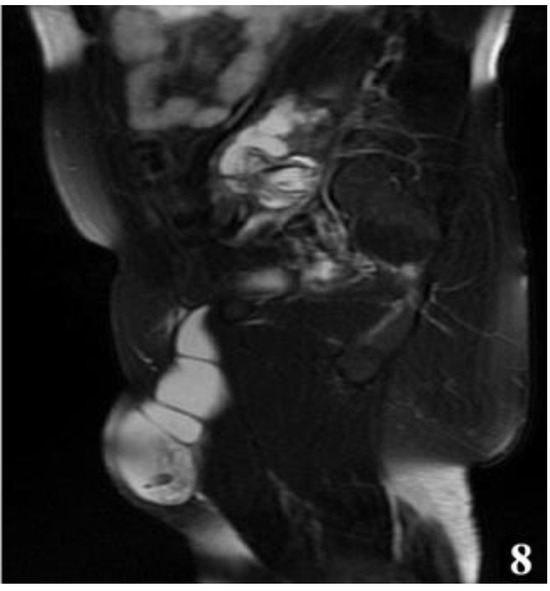

Figure 8.

T2W MRI sequence, sagittal—Hydatid cyst left iliopsoas muscle and left thigh (part 2).

Considering the impossibility of performing an ideal cystectomy, it was decided to perform an efficient drainage by closing the remaining retroperitoneal cavity after mounting a drain tube (through which the lavage and drainage slope at the base of the left thigh with tubes passed through the muscle gap is carried out). Adjacent peritoneal drainage and anatomical parietorrhaphy. Native MRI examination and post-operative intravenous post-contrast (Figure 17 and Figure 18), reveals: diffuse infiltrative-edematous appearance at the level of the iliopsoas muscle on the left side, with the presence of a collection with peripheral type gadophilia, difficult to appreciate under dimensional ratio, with a tendency to diffuse extension, developed predominantly intramuscularly at the level of the psoas muscle on the left side, with the predominant interest of its peripheral portion between 7–3 o’clock (being tangent to the external iliac vessels on the left side, with present, homogeneous flow at their level), extended to at the level of the ipsilateral iliac muscle and later in a caudal direction at the level of the iliopsoas muscle on the left side up to the vicinity of its distal insertion, after which it insinuates between the muscles of the antero-internal region of the thigh on the left side up to the border between the proximal third and the middle third of the thigh, and coming into contact on several sections with the femoral vessels on the left side, but without causing changes in caliber or flow at their level. At the level of the proximal portion there is a fistulous tract with a maximum thickness of approximately 0.7 cm, externalized at the level of the root of the left thigh in the antero-internal region which seems to communicate in depth with the previously described collection. In the proximal portion of the thigh on the left side, diffuse infiltrative-edematous changes adjacent to the previously described collection are evident at the level of the intermuscular space in the anterior region of the thigh, without being accompanied by similar changes at the level of the muscles in the anterior region of the thigh (Figure 17 and Figure 18).

Figure 17.

T2W sequence, sagittal—Postoperative residual hydatid cyst located at the level of the left iliopsoas muscle and deep to the left gluteus maximus muscle (part 1).

Figure 18.

T2W sequence, sagittal—Postoperative residual hydatid cyst located at the level of the left iliopsoas muscle and deep to the left gluteus maximus muscle (part 2).